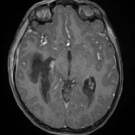

A previously healthy 8-year-old boy presented to the emergency department with sudden-onset neurological deficits and altered mental status following a syncopal episode.

12/27/2024